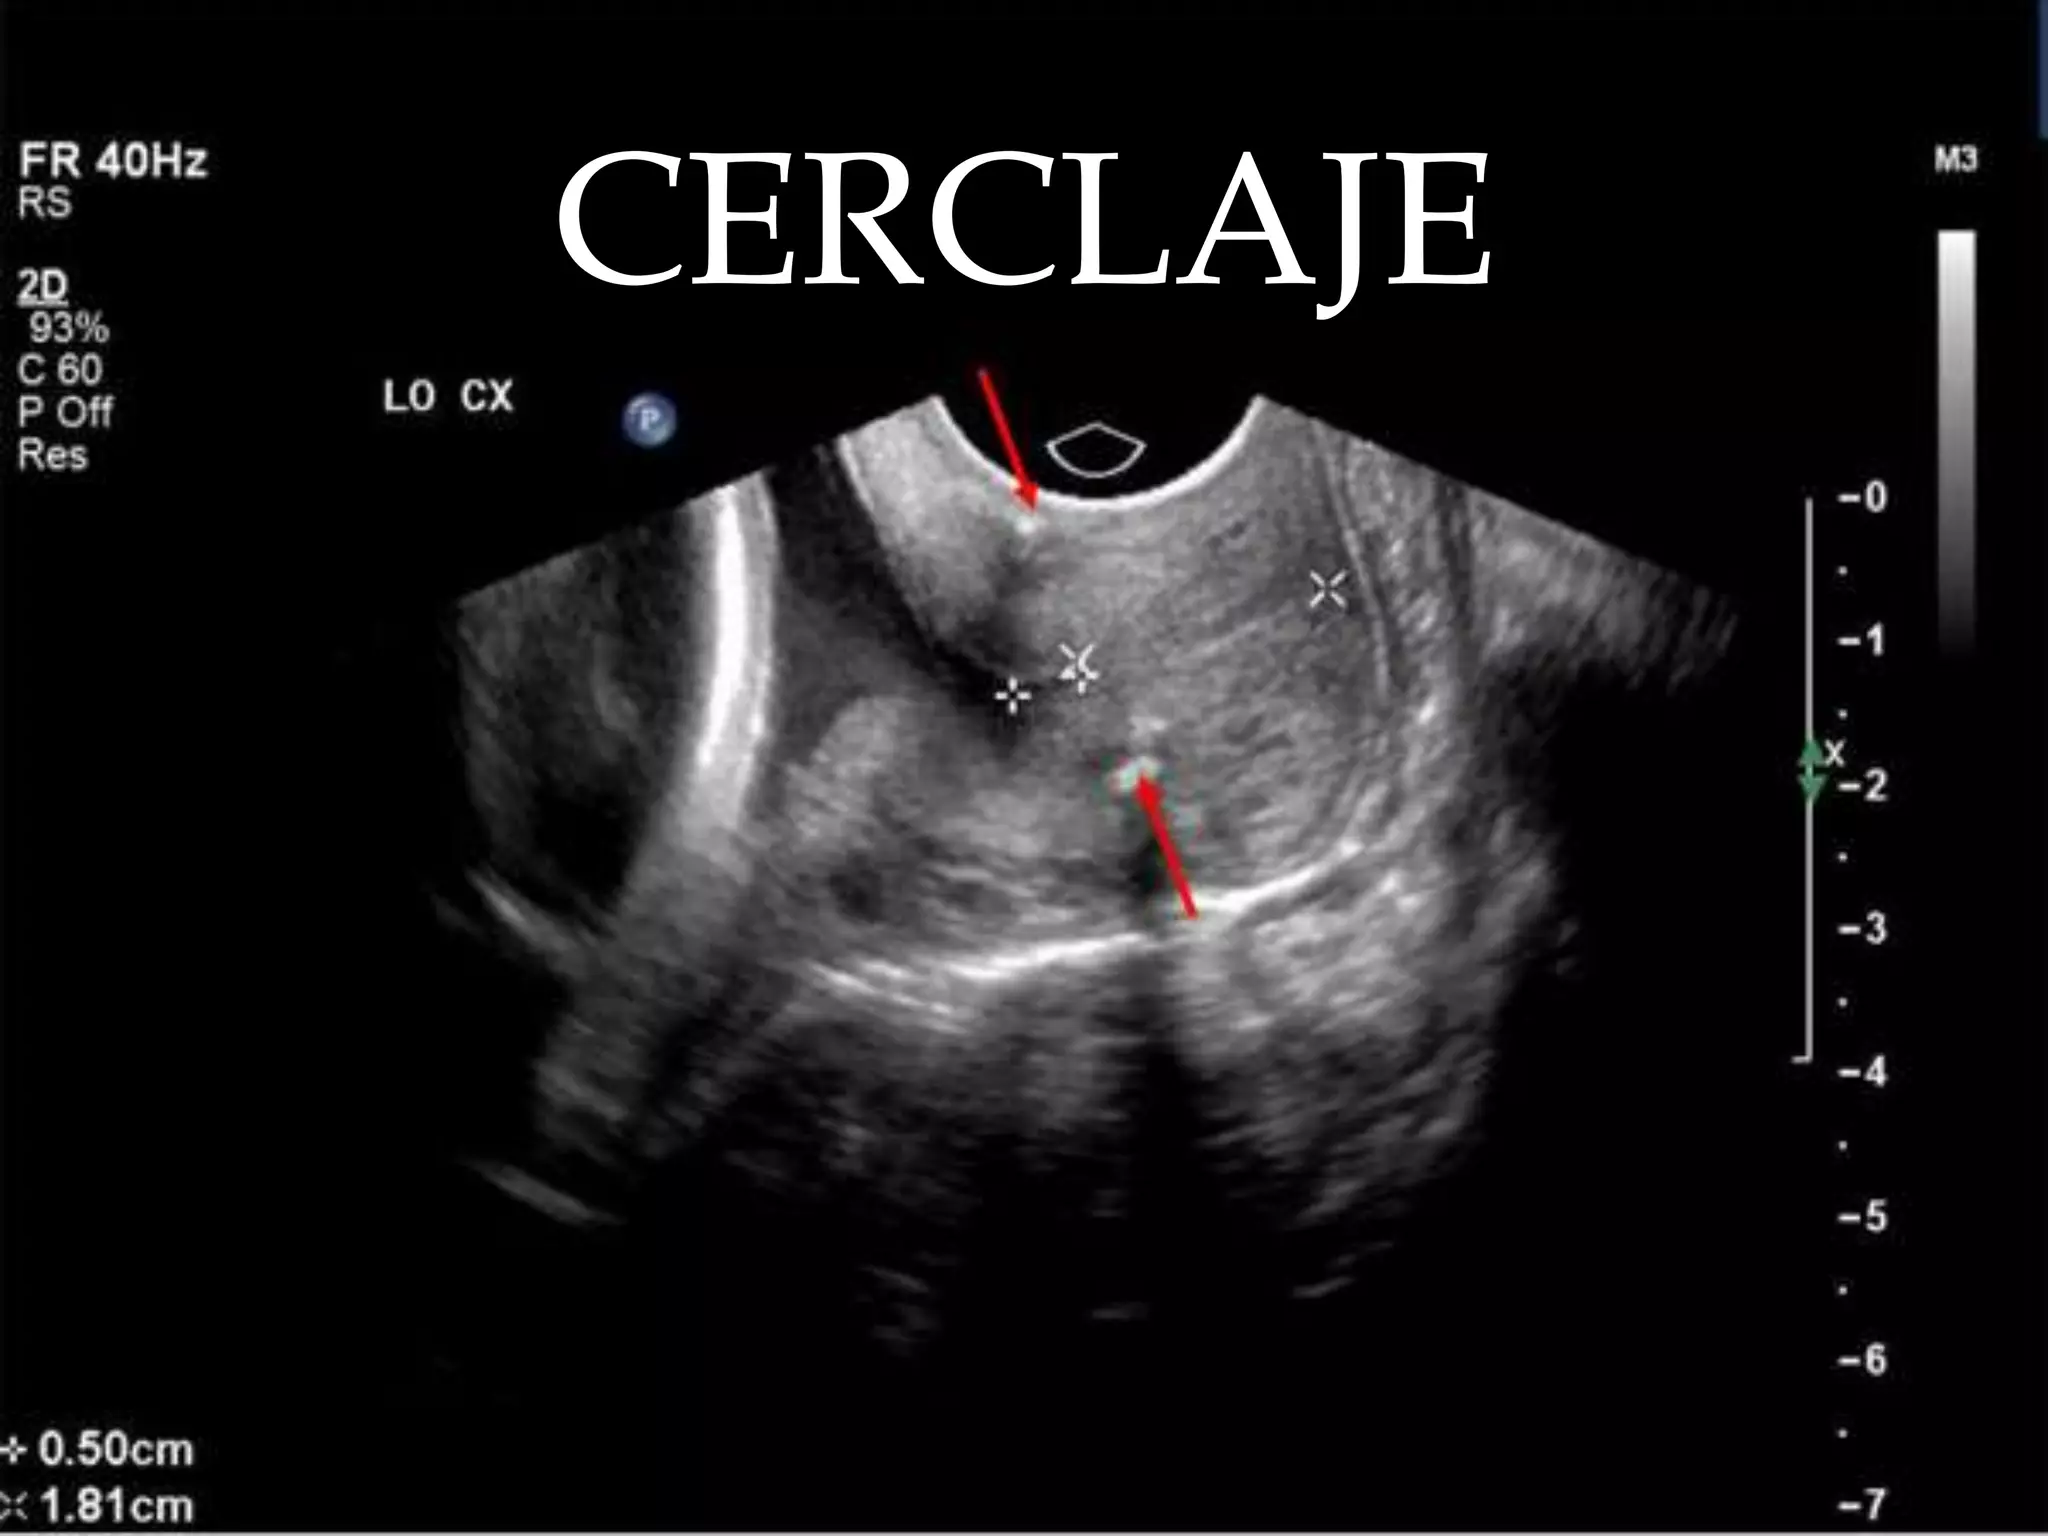

CERCLAJE

DEFINICIONSoporte  en el orificio interno de cérvix que lo haga continente del producto de la concepción hasta que sea viable o hasta que terminoDiferentes vías